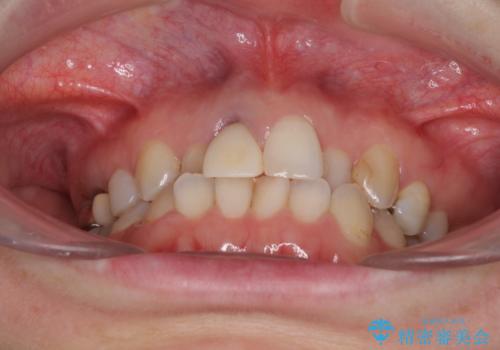

前歯のクロスバイトと治療が必要なむし歯 矯正とセラミックの総合歯科治療

- 前歯が痛いとのことで来院された患者様です。

前歯は根管治療が必要であったため、まずは根管治療を行いましたが、痛みが引いた後、矯正治療や前々から治療が必要と言われてきた歯を治療したいとのことでした。

前歯のクロスバイトはインビザラインで改善し、抜歯が必要な部分はインプラントを、その他むし歯が進行している歯はセラミッククラウンによる補綴治療することとしました。